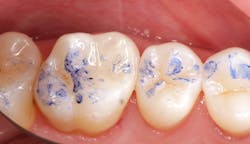

Inverting (no need to ligate teeth with floss)

The most important step to ensure a moisture-free dam that is well sealed and can retract the tissue is inverting the rubber dam. This step is performed after the dam has been flossed through the contacts and rinsed and dried. An explorer with air spray usually inverts most areas. When checking for inversion, floss the interproximals and hug the tooth while doing so; this will usually flip the dam over without inverting the explorer further.